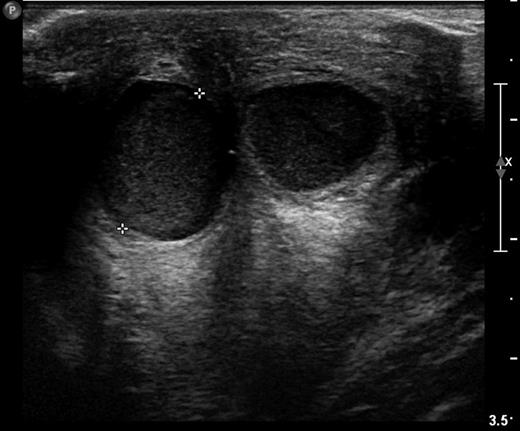

Sonography is the radiological modality that best characterizes retroareolar cysts [1, 4–6]. Garcia et al. [4] in a review of USS in the adolescent breast describe asymptomatic retroareolar cysts presenting as anechoic masses in the breast tissue. The cysts can be multiple in number, round or lobular in shape and contain internal septations or isolated echoes (Fig. 1; [4, 5]). Garcia et al. [4] further describe inflammatory retroareolar cysts to contain echogenic debris, fluid filled levels, internal septations and increased peripheral vascularity [4]. This correlates with our sonographic findings (Fig. 2) and Huneeus et al.'s [1] series who noted the enhanced vascularity only in the symptomatic cyst [1]. Interestingly, Huneeus et al. [1] also reported the presence of bilateral asymptomatic cysts in almost half of their patients.